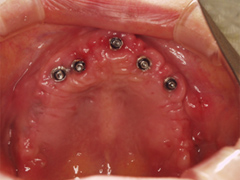

(1)オールオン4インプラント治療を行う

総入れ歯をされていた患者さまの場合は、その入れ歯を使い続けていたことによる骨や歯茎が退縮しやせてしまっている。インプラントを入れても半年間はまともに咬むことができない場合が多い。

手術したその日からまともに食事ができるように手術したその日に仮の歯を入れる。

写真(1)